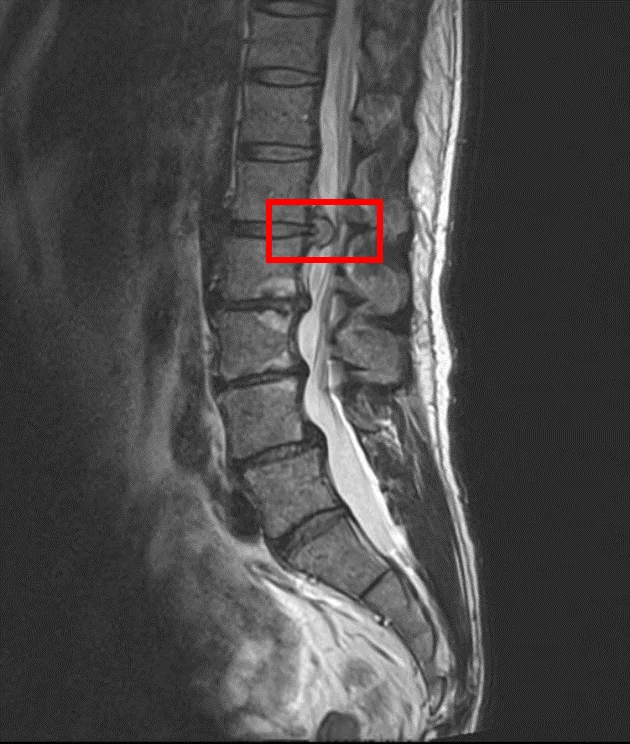

По данным МРТ и результатам осмотра пациента выявлена межпозвоночная грыжа диска L1/L2 и дегенерация дисков L2/L3, L3/L4, L4/L5.

В клинике проведена селлгель-терапия на 4 межпозвоночных дисках (L1/L2, L2/L3, L3/L4, L4/L5).